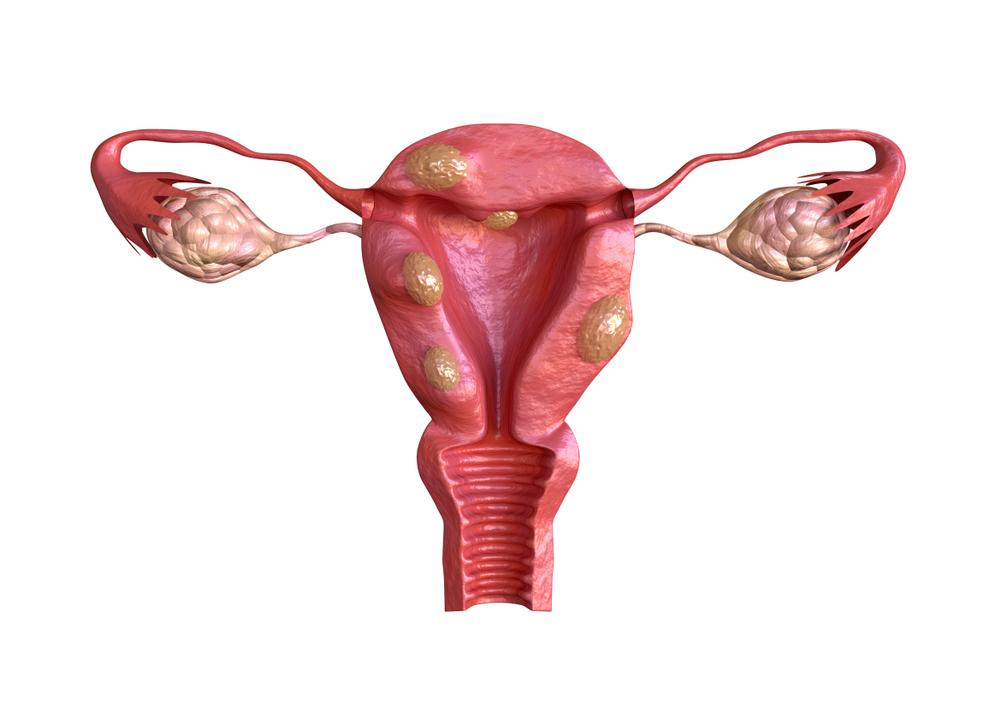

U xơ tử cung là một bệnh lành tính thường gặp nhưng khiến nhiều phụ nữ lo sợ. Mặc dù có rất nhiều phương pháp điều trị u xơ tử cung, nhưng các triệu chứng của bệnh lại không dễ phát hiện nên nhiều người không biết mình đã mắc bệnh để tiếp nhận việc điều trị. U xơ tử cung có biến chứng nếu không được chữa trị kịp thời có thể dẫn đến những hậu quả nguy hiểm. Vậy, biến chứng u xơ tử cung là gì?

Mặc dù hầu như các trường hợp mắc bệnh u xơ tử cung đều là lành tính và hiếm khi dẫn đến ung thư, nhưng các biến chứng u xơ tử cung đều ảnh hưởng nghiêm trọng đến sức khỏe, thậm chí là tính mạng của người bệnh. Trong bài viết này, Hello Bacsi đề cập 7 biến chứng u xơ tử cung phổ biến để bạn tham khảo.